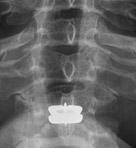

Figura 2. Radiografía articulación atlantoaxoidea . En una proyección AP se extiende el cuello de forma que el occipucio y los dientes superiores se sitúan en el mismo plano . Esta radiografía muestra las relaciones del atlas y el axis. Los ligamentos de la articulación atlantoaxoidea son radiotransparentes y por lo tanto no ofrecen ninguna sombra. Las masas laterales del atlas son de forma triangular y fácilmente reconocibles . En la parte lateral , las largas apófisis transversas del atlas son claramente visibles . Entre las masas laterales se aprecia el diente del axis